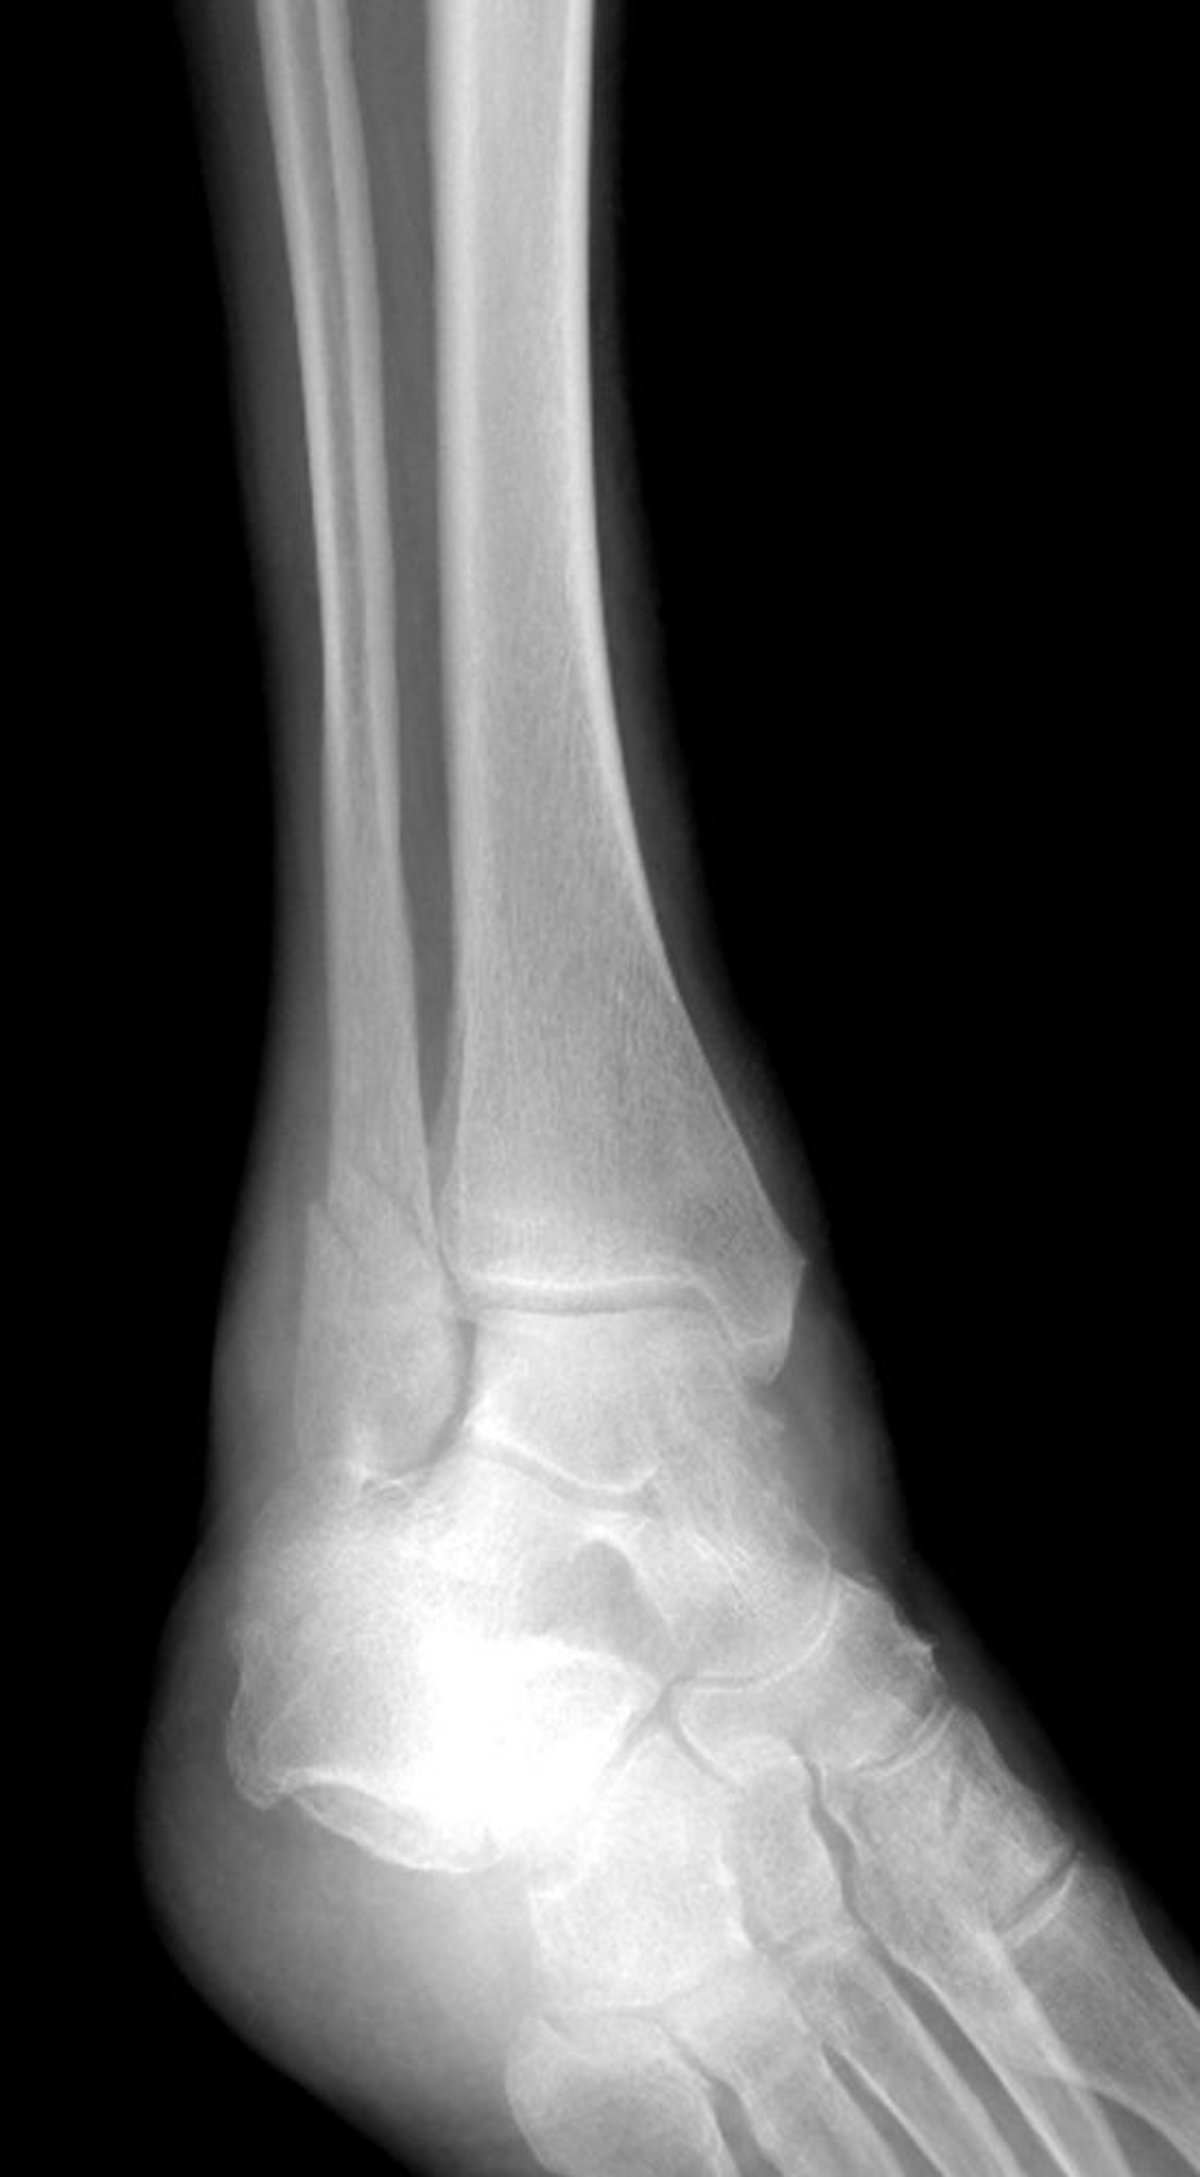

Це перелом латеральної кісточки, але поєднаний із переломом медіальної кісточки.

LIVING ART ENTERPRISES, LLC/НАУКОВА ФОТОБІБЛІОТЕКА